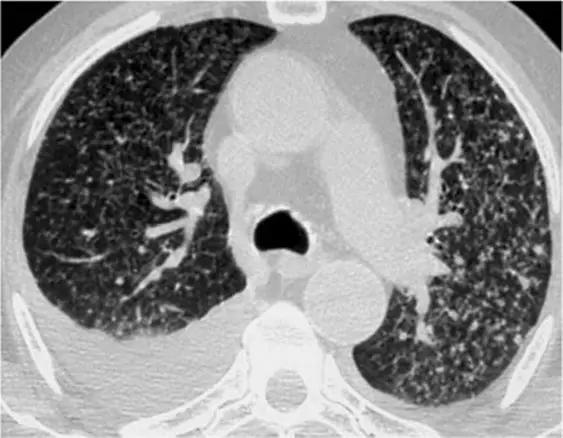

5、磨玻璃影-网状影混杂模式

有时,在肺部同一区域中可能同时存在磨玻璃样影和网状影共存,这种组合几乎等同于不可逆的纤维化。典型疾病:是非特异性间质性肺炎(NSIP)。表现为磨玻璃影改变为主、轻度网状改变。鉴别疾病:硬皮病、特发性肺纤维化(IPF)和脱屑性间质性肺炎(DIP)。

硬皮病的肺部侵袭类似于NSIP,因为它是最常见的组织学类型的纤维化。有利于硬皮病的主要发现是食管扩张和肺动脉扩张。

*硬皮病。下叶水平的HRCT表现为混合的“磨玻璃样和网状样”,其特征是磨玻璃样改变和牵引性支气管扩张。请注意5 mm胸膜下不受累,这是硬皮病最常见的组织学类型NSIP的特征相关性肺纤维化。